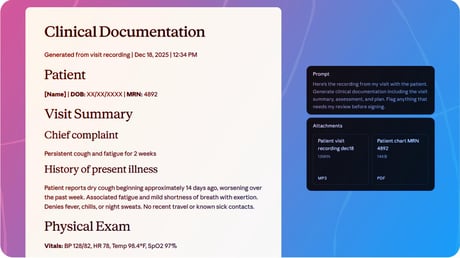

A mesterséges intelligencia mostantól megfejti az orvosi leleteidet

Érdemes megérteni, hogy az Anthropic új, Claude for Healthcare nevű MI-asszisztense mostantól a saját egészségügyi csapatod része lehet: segít jobban átlátni az orvosi...

Az egészségügy forradalmát hozza el Claude, berobban az MI

Az Anthropic elhozta Claude-ot az egészségügybe, ezzel felveszi a versenyt az OpenAI ChatGPT-jével. Az MI mostantól, a kifejezetten kórházak és biztosítók igényeihez fejlesztett...